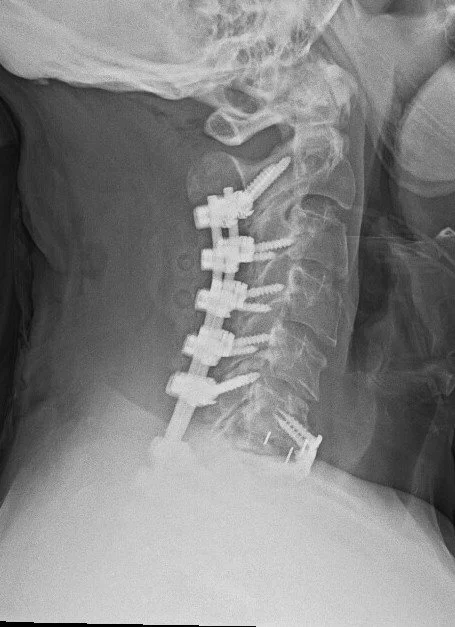

Cervical Spine Revision Surgery

Revision of a cervical spine surgery can be needed for a variety of reasons: failure for bones to fuse (cervical pseudoarthrosis), malposition or failure of implanted hardware, inadequate decompression of the spinal cord or nerve roots, new or persistent neck pain or cervical radiculopathy or myelopathy symptoms, degeneration of neighboring spinal segments, infection, spinal instability, and others.

Management options for a failed cervical surgery might include ACDF, cervical corpectomy, CORUS cervical fusion, or posterior cervical fusion, among others. Each of these options has benefits and drawbacks. The right surgery for you will depend on your symptoms, your previous surgery, the number of spinal levels affected, and factors related to your medical history, age, smoking status, and spinal anatomy.